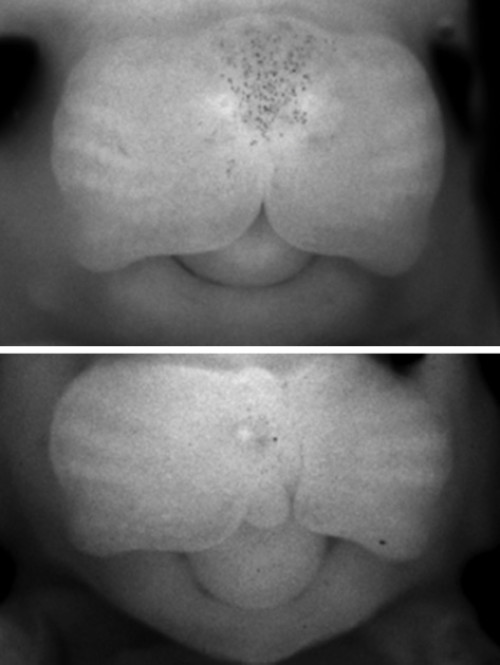

唇腭裂是一種賊常見的出生缺陷,可以唇裂或腭裂其中一種形式單獨出現(xiàn),也可以唇裂和腭裂兩種形式共同出現(xiàn)。它們也能夠與其它畸形一起發(fā)生,形成一種綜合癥。根據《人的基因序列變化與人體疾病表征》,共有超過350種具有不同臨床表現(xiàn)的唇腭裂綜合征,而且大約每500到1000名新生兒中就有一例出現(xiàn)。唇裂,伴有或不伴有腭裂(CL/P),都是人類常見的一種先天性畸形。自古就有,而用自從開始在人類中出現(xiàn),就會附會以不同的解釋。其中的一些是經驗的積累,另外是關于其發(fā)生的猜測??偟膩碚f, 不具備分子生物學或者是基因解碼知識的人,即使是臨床醫(yī)生,也會認為唇腭裂與基因無關,但是基因解碼是一種比基因檢測更為先進的理解基因作用的知識和技術體系,更清楚地揭示這種畸形是基因的作用方式發(fā)生異常的結果。

什么是唇裂?

唇腭裂是一個通俗的說法,它是指在人的是唇和顎部有裂口。其實這個名稱并不能代表顱面部全部先天畸形。還包括牙槽突裂,另外還有有效性的唇裂還包括鼻底的裂開。再有由于牙槽突裂的存在,還會導致牙齒在發(fā)育當中的一個畸形。這種畸形它會影響到口腔和面部的很多的器官和功能。另外由于腭裂存在,還會影響到患者的聽力。因此唇腭裂畸形是系統(tǒng)性、可能會影響多個方面的病變。這種病變一般來說是由于在發(fā)育過程中,由某種因素而導致形成口腔和面部發(fā)育的一些生發(fā)中心沒有正常的連接和融合所導致的。唇腭裂是一種非常常見的先天的頜面部的發(fā)育畸形,一般來說在正常人群里面就達到1-2‰。亞州人群高于非洲人群?;蛘呤?00-700個人當中就會有一個唇腭裂小孩的發(fā)生。這種唇腭裂會在妊娠前的前三個月就出現(xiàn),由于各種各樣的因素,而影響胚胎的發(fā)育。這種畸形會影響到我們小朋友,除了形態(tài)和功能以外,它的影響還是非常深遠。包括未來的發(fā)音,還有頜面部骨骼的發(fā)育,還有外形和功能的一些畸形和不正常。還有可能會影響到他參與社會行為,一些社會交往,反過來還會影響他的心理發(fā)育。因此這種唇腭裂的畸形是需要我們特別關注的。在胚胎發(fā)育的早期,唇、腭是由兩側組織往身體中線融合起來的,若不能正常融合,就會產生各種不同部位的裂縫,單純嘴唇裂開,稱為唇裂,既有唇部裂開又有腭部裂開稱為唇腭裂,有時僅口腔內腭部裂開而外部正常,則稱為腭裂。